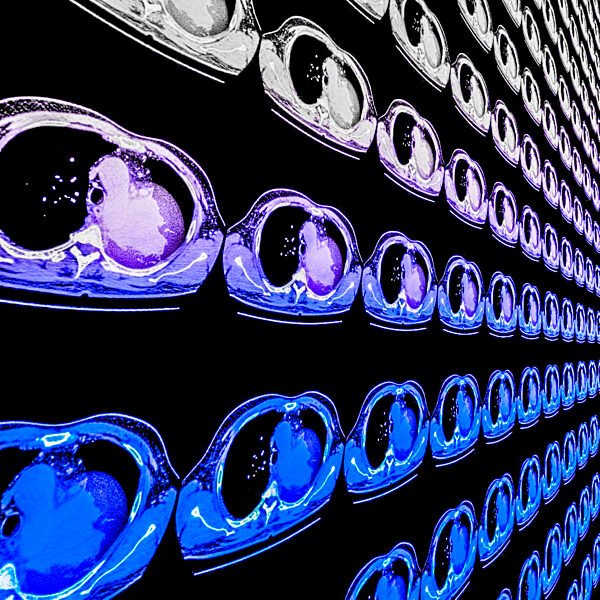

01.01.1000 - Coloured computed tomography (CT) scans of lung cancer, showing a solid mass (pink, centre right). This is a carcinoma, a type of cancer that arises from the epithelial tissue that...

560495573